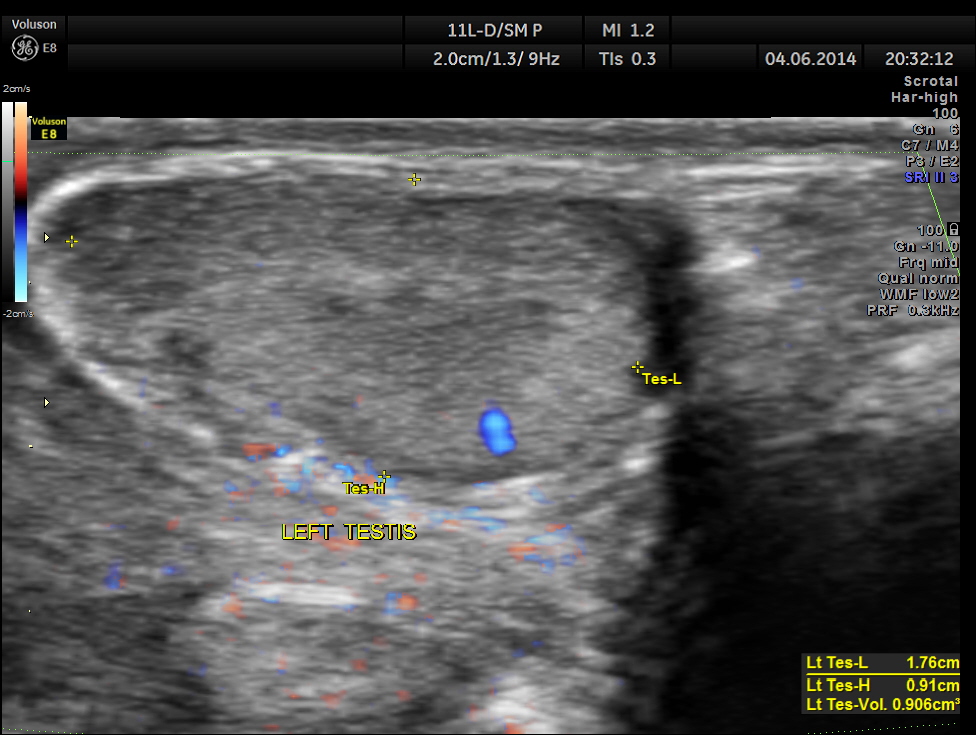

The images of the left testis are given below for comparison.

This was a case of acute epididymitis , without orchitis . In our part of the world filarial infestation leading to acute epididymitis is a common occurrence .